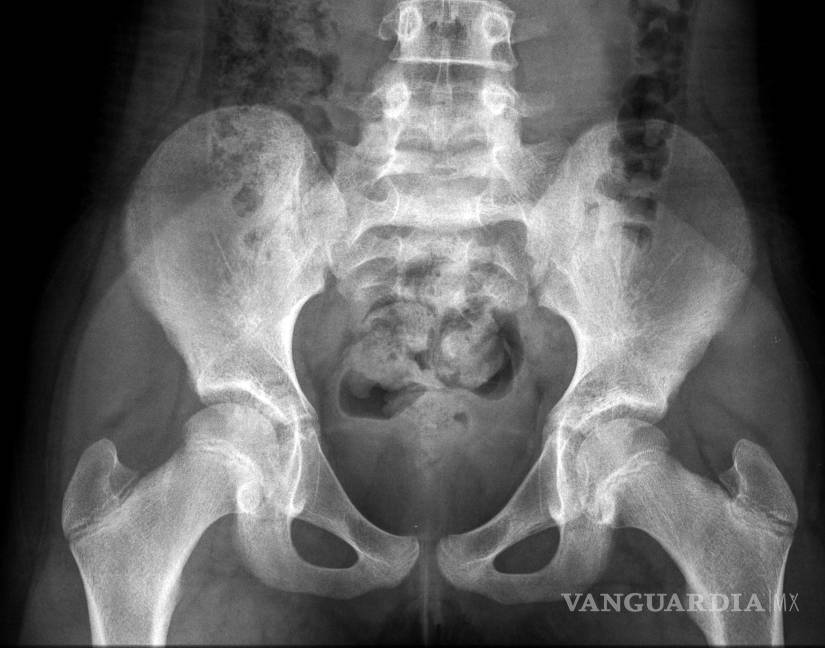

El principal problema es que la pelvis de las niñas es demasiado estrecha como para que pueda pasar incluso un feto pequeño, señaló Ashok Dyalchand, un médico que ha trabajado con adolescentes embarazadas en comunidades de bajos ingresos en la India durante más de 40 años.

“La labor de parto que experimentan es prolongada y obstruida, el feto aplasta la vejiga y la uretra” y a veces provoca la enfermedad pélvica inflamatoria y la ruptura de los tejidos que hay entre la vagina y la vejiga y el recto, señaló Dyalchand, quien dirige el Instituto de Gestión Sanitaria Pachod, que es una organización de salud pública que atiende a las comunidades marginadas en la zona central de la India.

En los casos que él ha visto, el embarazo temprano frena el desarrollo físico de las madres muy jóvenes y, con frecuencia, también el desarrollo mental debido a que muchas niñas dejan la escuela y se pierden de la interacción social normal con sus compañeros, comentó Syed. Pero, pese a que una madre anémica tiene problemas para llevar el embarazo, el feto se apropia de los nutrientes y sigue creciendo hasta que supera por mucho lo que puede dejar pasar la pelvis de una madre muy joven.

“Las chicas pasan por un trabajo de parto de tres, cuatro, cinco días y después de ese tiempo, el bebé casi siempre está muerto. Y el bebé sale cuando se hunde la cabeza”, explicó Syed, quien es uno de los especialistas más prominentes de Asia del Sur en la reparación de la fístula obstétrica, un resultado habitual del parto obstruido en las niñas embarazadas.

En casi todos estos casos, la niña desarrolla una fístula vesicovaginal, que es un agujero entre la pared de la vejiga y la vagina. En una cuarta parte de los casos, el trabajo de parto prolongado también origina una fístula del recto, por lo que la chica deja salir orina y excremento de manera constante.